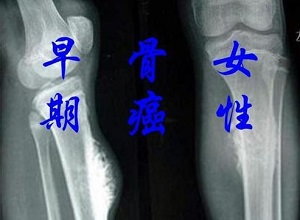

郑州看肿瘤中医馆哪家好?骨癌来临时身体会出现这5大症状.骨癌,也称为恶性骨肿瘤,是一种发生在骨骼和附属组织中的肿瘤疾病。骨癌通常发展迅速,死亡率相对较高。然而,骨癌的早期症状通常不是很明显。只有随着疾病的发展,许多症状才逐渐明显。当疾病发展到一定程度时,许多患者会出现局部疼痛和肿胀,但此时往往较晚。因此,骨癌发现得越早越好。虽然早期症状并不明显,但你可以更多地关注你的身体状况。

那么骨癌的临床表现是什么呢?

郑州看肿瘤中医馆哪家好?骨癌来临时身体会出现这5大症状.骨癌不是一种很常见的疾病,儿童和年轻人的发病率高于老年人。骨癌的发展也与环境有关。因此,我们应该关注我们的日常生活环境。一旦出现相关症状,应及时到医馆治疗。